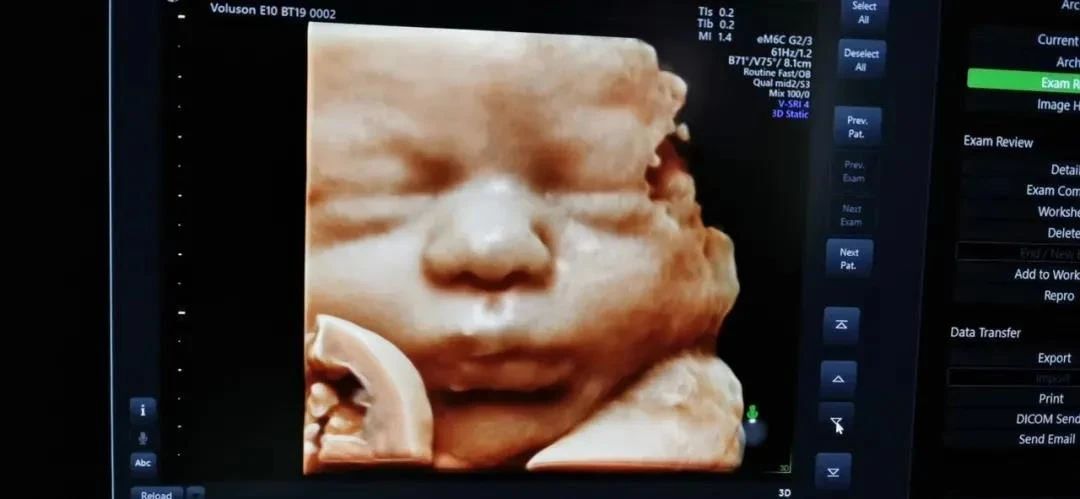

其次,安琪儿使用的彩超设备是GE-E10,也是成都更早拥有GE-E10的医疗机构,胎儿排畸检查更强大,独立成像更清晰。孕妈妈还可以通过四维彩超获得宝宝人生第一张照片哦!